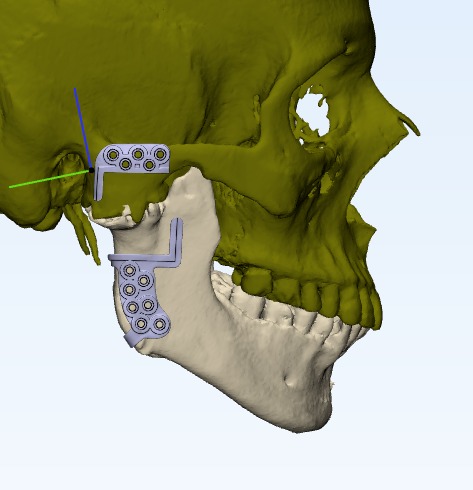

Tmj anklosys leading to deficient mandible and deficient chin corrected by TMJ Surgery followed by Orthognathic surgery